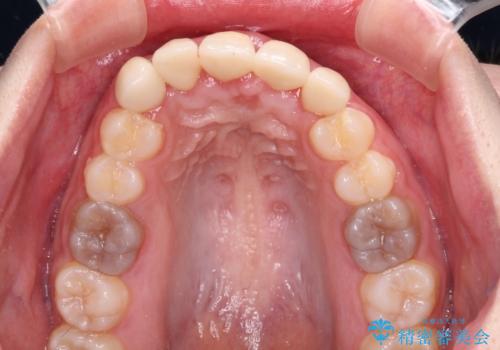

金属の裏打ちを用いたセラミッククラウンであったため歯肉縁に黒ずみが見えてくることは良くありますが、全体的に歯列が不揃いであることが気になったので、それらをオールセラミッククラウンにて改善することとしました。

オールセラミッククラウン装着後、レントゲン写真より精度良く装着されていることは確認できているので、日頃のブラッシングで改善させるよう指導しています。